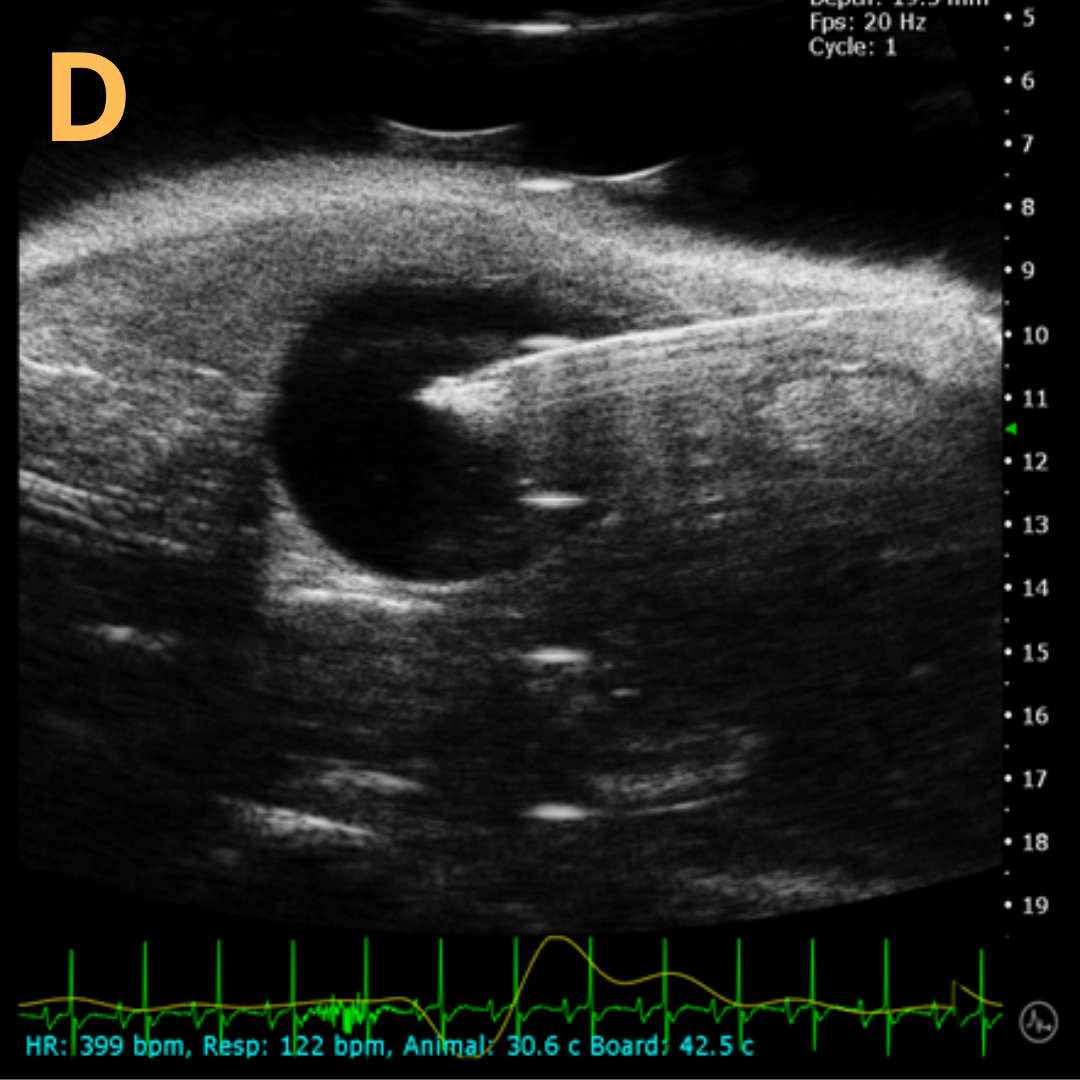

Ultrasound-Guided Injection

This is A) a B-mode video showing an injection into the bladder with B – D being still frames of B) before injection of any solution with the landmarks noted, C) during injection with bladder becoming notably larger, and D) the end of injection before needle will be removed. Imaging on a wildtype C57B6J mouse model – acquired images are from Stephen Zderic’s lab at the Children’s Hospital of Philadelphia.